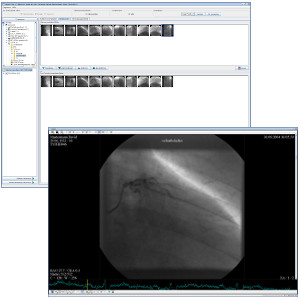

TM-PACS

Permette di comprimere, proteggere, salvare e visualizzare immagini radiologiche con strumenti di visualizzazione all'avanguardia (zoom, lente di ingrandimento, annotazioni, misurazione delle distanze, monitoraggio delle misurazioni ecc.). L'utente può visualizzare immagini angiografiche coronariche, immagini PET di medicina nucleare e le più tradizionali immagini (MRI, TC, ecografiche ecc.). L'applicazione di etichette consente di formare gruppi di esami e di accedervi tramite un semplice clic. Un sistema di ricerca personalizzato recupera rapidamente la cartella del paziente o l'esame desiderato. La soluzione è ottimizzata per la visualizzazione multischermo con integrazione dei software RIS e PACS, installati presso le stesse stazioni di diagnosi.